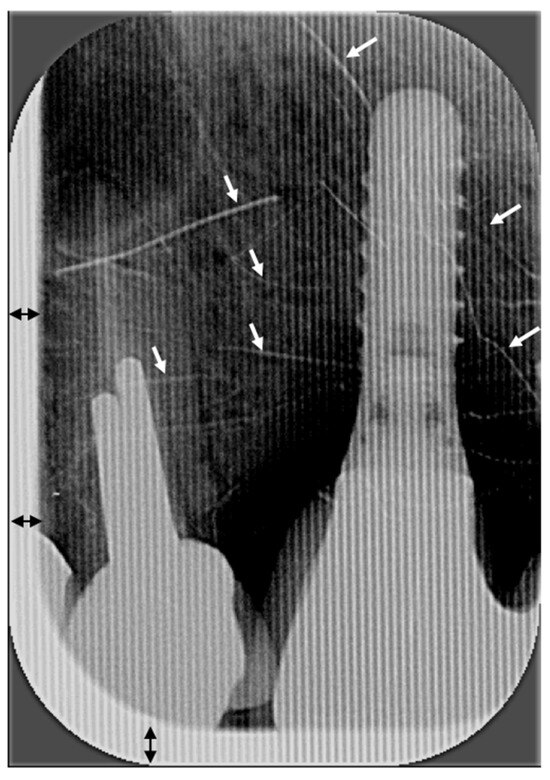

- Clark-Perry, D.; Berkhout, W.E.R.; Sanderink, G.C.; Slot, D.E. Evaluating cone cut in rectangular collimation in intraoral radiography: Application of ALADA and radiation stewardship. Clin. Oral Investig. 2023, 27, 5391–5402. [Google Scholar]

- Horton, P.S.; Sippy, F.H.; Nelson, J.F.; Kohout, F.J.; Kienzle, G.C. A comparison of rectangular and cylindrical collimation for intraoral radiographs. J. Dent. Educ. 1983, 47, 771–773. [Google Scholar] [CrossRef] [PubMed]

- Parrott, L.A.; Ng, S.Y. A comparison between bitewing radiographs taken with rectangular and circular collimators in UK military dental practices: A retrospective study. Dentomaxillofacial Radiol. 2011, 40, 102–109. [Google Scholar] [CrossRef] [PubMed]